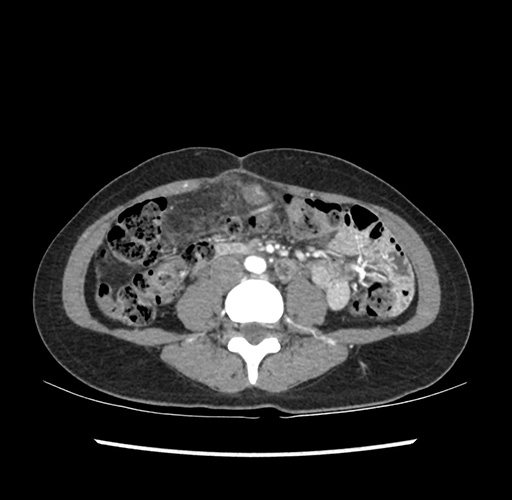

Imaging Analysis

Look through the patient's CT scan to identify any areas of concern for the necessary procedure.

Based on your CT findings, which issue(s) would give reason for "planned slowing down moment(s)" in this case?

Considering a standard left lateral sectionectomy procedure, what step(s) of the operation would you do differently in this case ?